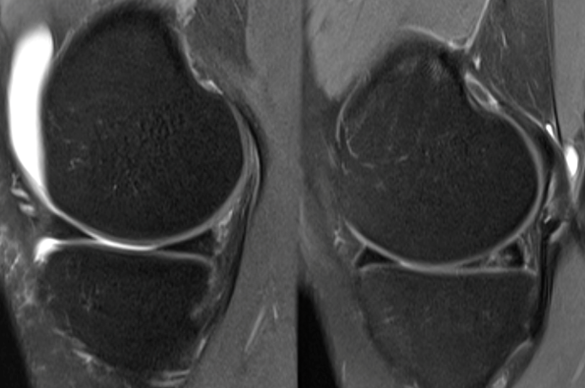

B) Meniskusnaht – den Meniskus erhalten statt entfernen

Die Meniskusnaht ist ein arthroskopisches, gelenkerhaltendes Verfahren, bei dem der eingerissene Meniskusanteil mit feinen Nahttechniken fixiert wird. Ziel ist es, den Meniskus in seiner ursprünglichen Form zu rekonstruieren, damit er seine wichtige Funktion als Stoßdämpfer und Gelenkstabilisator weiterhin erfüllen kann.

Daher ist die Meniskusnaht vor allem bei frischen Rissen in der gut durchbluteten Zone des Meniskus eine sehr sinnvolle Option – dort, wo die Heilungschancen am höchsten sind.

Voraussetzungen für eine erfolgreiche Meniskusnaht:

2. Operative Therapie (arthroskopisch)

Dabei kommen zwei Verfahren infrage:

A) Meniskusteilresektion

Bei der Meniskusteilresektion wird der beschädigte Teil des Meniskus mit feinen arthroskopischen Instrumenten entfernt. Anschließend wird der verbleibende Meniskus geglättet, um weitere Risse zu vermeiden.